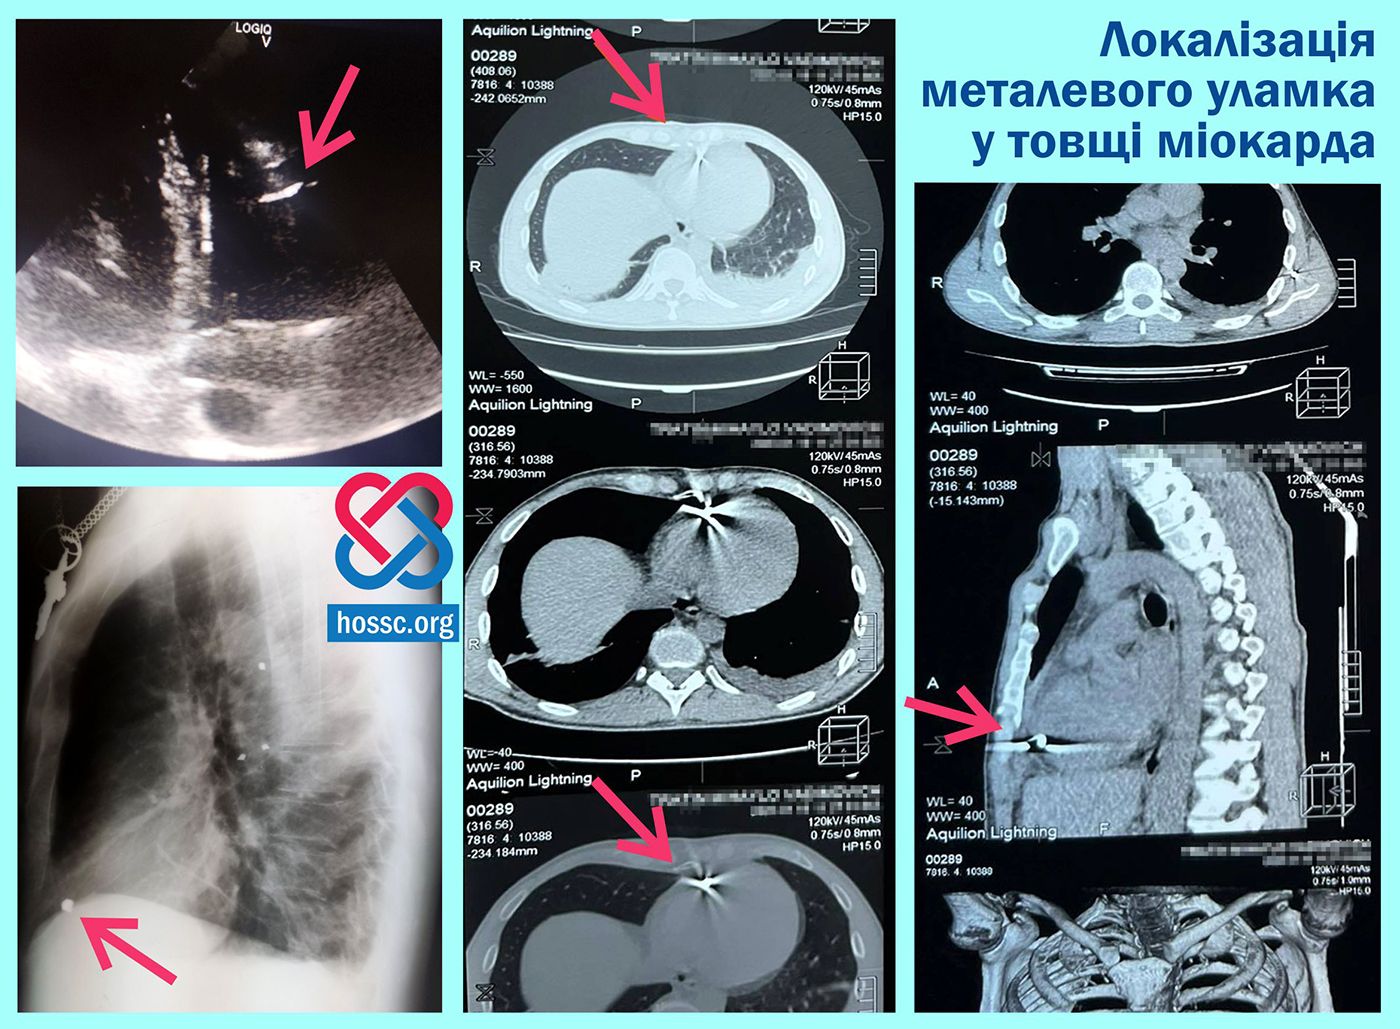

– За результатами обстеження, ехокардіоскопії та комп’ютерної томографії, нашими фахівцями була встановлена точна локалізація – у товщі міокарда правого шлуночка, – розповідають хмельницькі лікарі.

37-річний захисник України з Тернополя зазнав тяжких поранень під час виконання бойового завдання на Дніпропетровщині. Уламок від вибухової міни діаметром понад 1 см потрапив прямісінько у серце військового. Фронтові медики оперативно надали йому невідкладну допомогу та відправили до Хмельницького обласного центру серцево-судинної хірургії.